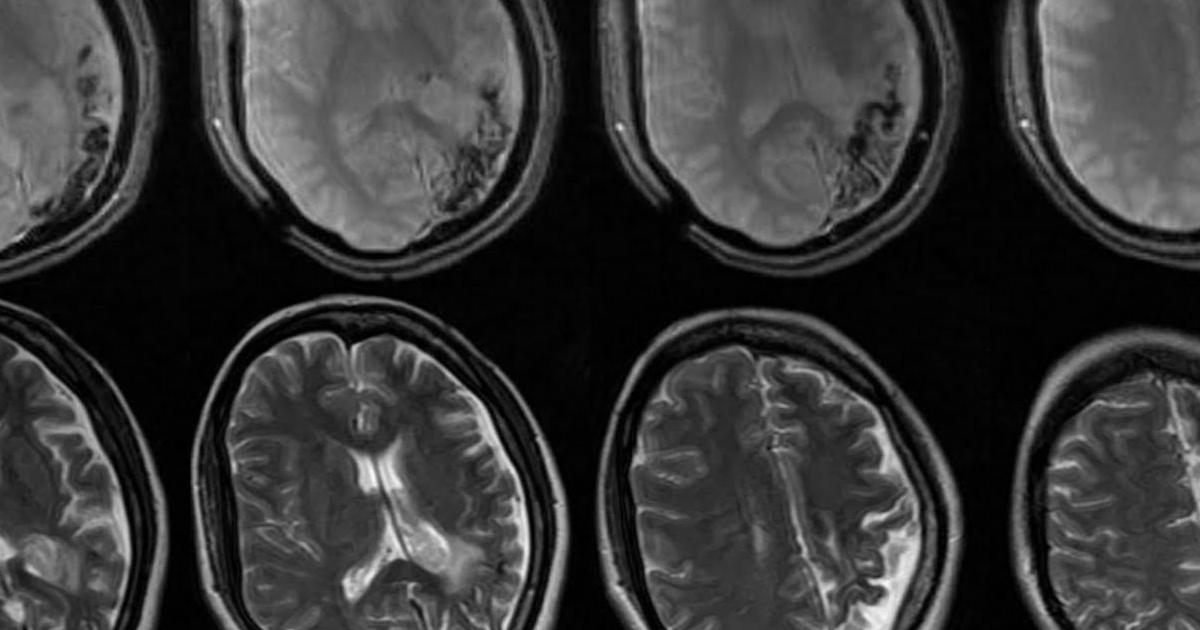

Angiomyolipoma is strongly associated with tuberous sclerosis, a genetic disease in which most individuals develop angiomyolipomas on one or both kidneys. This genetic disorder is rare and affects multiple bodily systems, causing benign tumors to develop in vital organs such as the brain, eyes, lungs, and kidneys. It can also cause other symptoms such as behavioral issues, developmental delay, intellectual delay, kidney disease, and skin abnormalities. More than fifty percent of patients with tuberous sclerosis (TS) also develop angiomyolipoma.

It is common for people with TS to require at least one form of intervention over their lifetime to treat tumors. Considering TS can impair kidney function, it is possible for the kidney to lose up to half of its function before the loss is detectable. Treatment usually involves embolization to shrink the tumor and reduce the risk of bleeding.